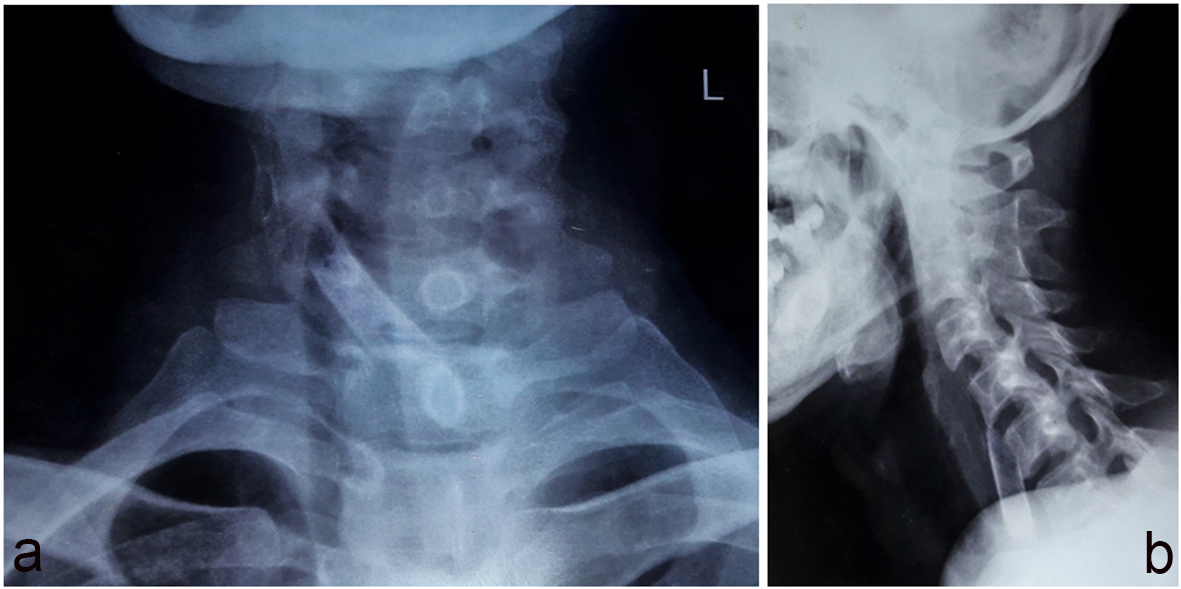

On examination, the patient looked toxic and dehydrated. His voice was muffled. His blood pressure was 100/50 mm Hg, and pulse rate was 110/min regular with low volume. His temperature was 102 °F. His white blood cell (WBC) count was 14,000 mg/dL. His blood urea was 91 g/dL, while creatinine was 2.1 g/dL. There was no abnormal finding in the oral cavity. Indirect laryngoscopy revealed positive Chevalier Jackson’s sign. There was fullness over anterior aspect of neck. There was a rise of temperature and tenderness on palpation. Lymph nodes were not palpable. X-ray soft tissue neck lateral and AP views revealed a huge radiopaque foreign body extending from the level of lower border of C5-C7 vertebra (Fig. 1). There was no free air in mediastinum.

![]() Click for large image | Figure 1. (a) Plain X-ray AP view showing radioopaque shadow. (b) Plain X-ray lateral view showing radiopaque shadow from C5 to C7 level. |